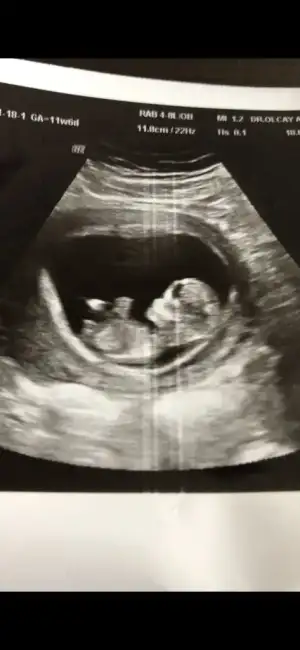

Erkek görünüyorMerhaba 11+6 tahmin edermisiniz

Net değil nubu emin olamadim başka USG varsa paylaşın sanki kız ama emin değilimMerhaba 12 haftalık tahmin edebilir misiniz![]()